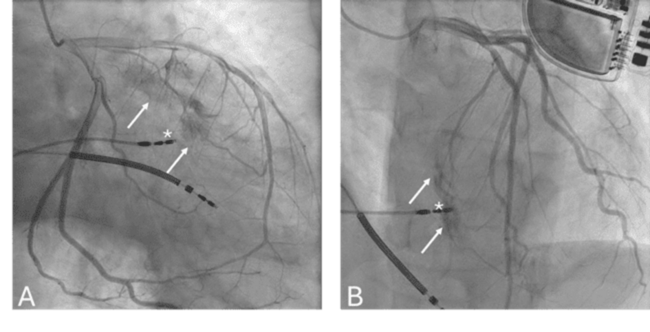

Septal Coronary Artery Fistula After Implantation of a Left Bundle Branch Area Pacemaker

Video Supplement to "Septal Coronary Artery Fistula After Implantation of a Left Bundle Branch Area Pacemaker" (Clinical Image).